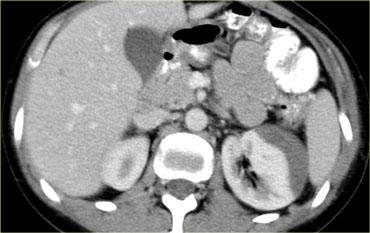

Bên trái là hình ảnh của một nam giới 65 tuổi bị xe ô tô đâm ở tốc độ vừa phải.

Mất ý thức trong 2 phút.

Đặt thông tiểu Foley và phát hiện đái máu đại thể.

Phim X-quang cho thấy gãy xương mu di lệch vừa với các mảnh xương nhọn ở vùng bàng quang.

Bên trái là hình ảnh CT chấn thương thường quy.

Nhận xét các dấu hiệu hình ảnh?

Có hình ảnh gãy xương chậu di lệch với một mảnh xương nhọn hướng về phía bàng quang.

Có dịch trong khoang trước bàng quang (khoang Retzius).